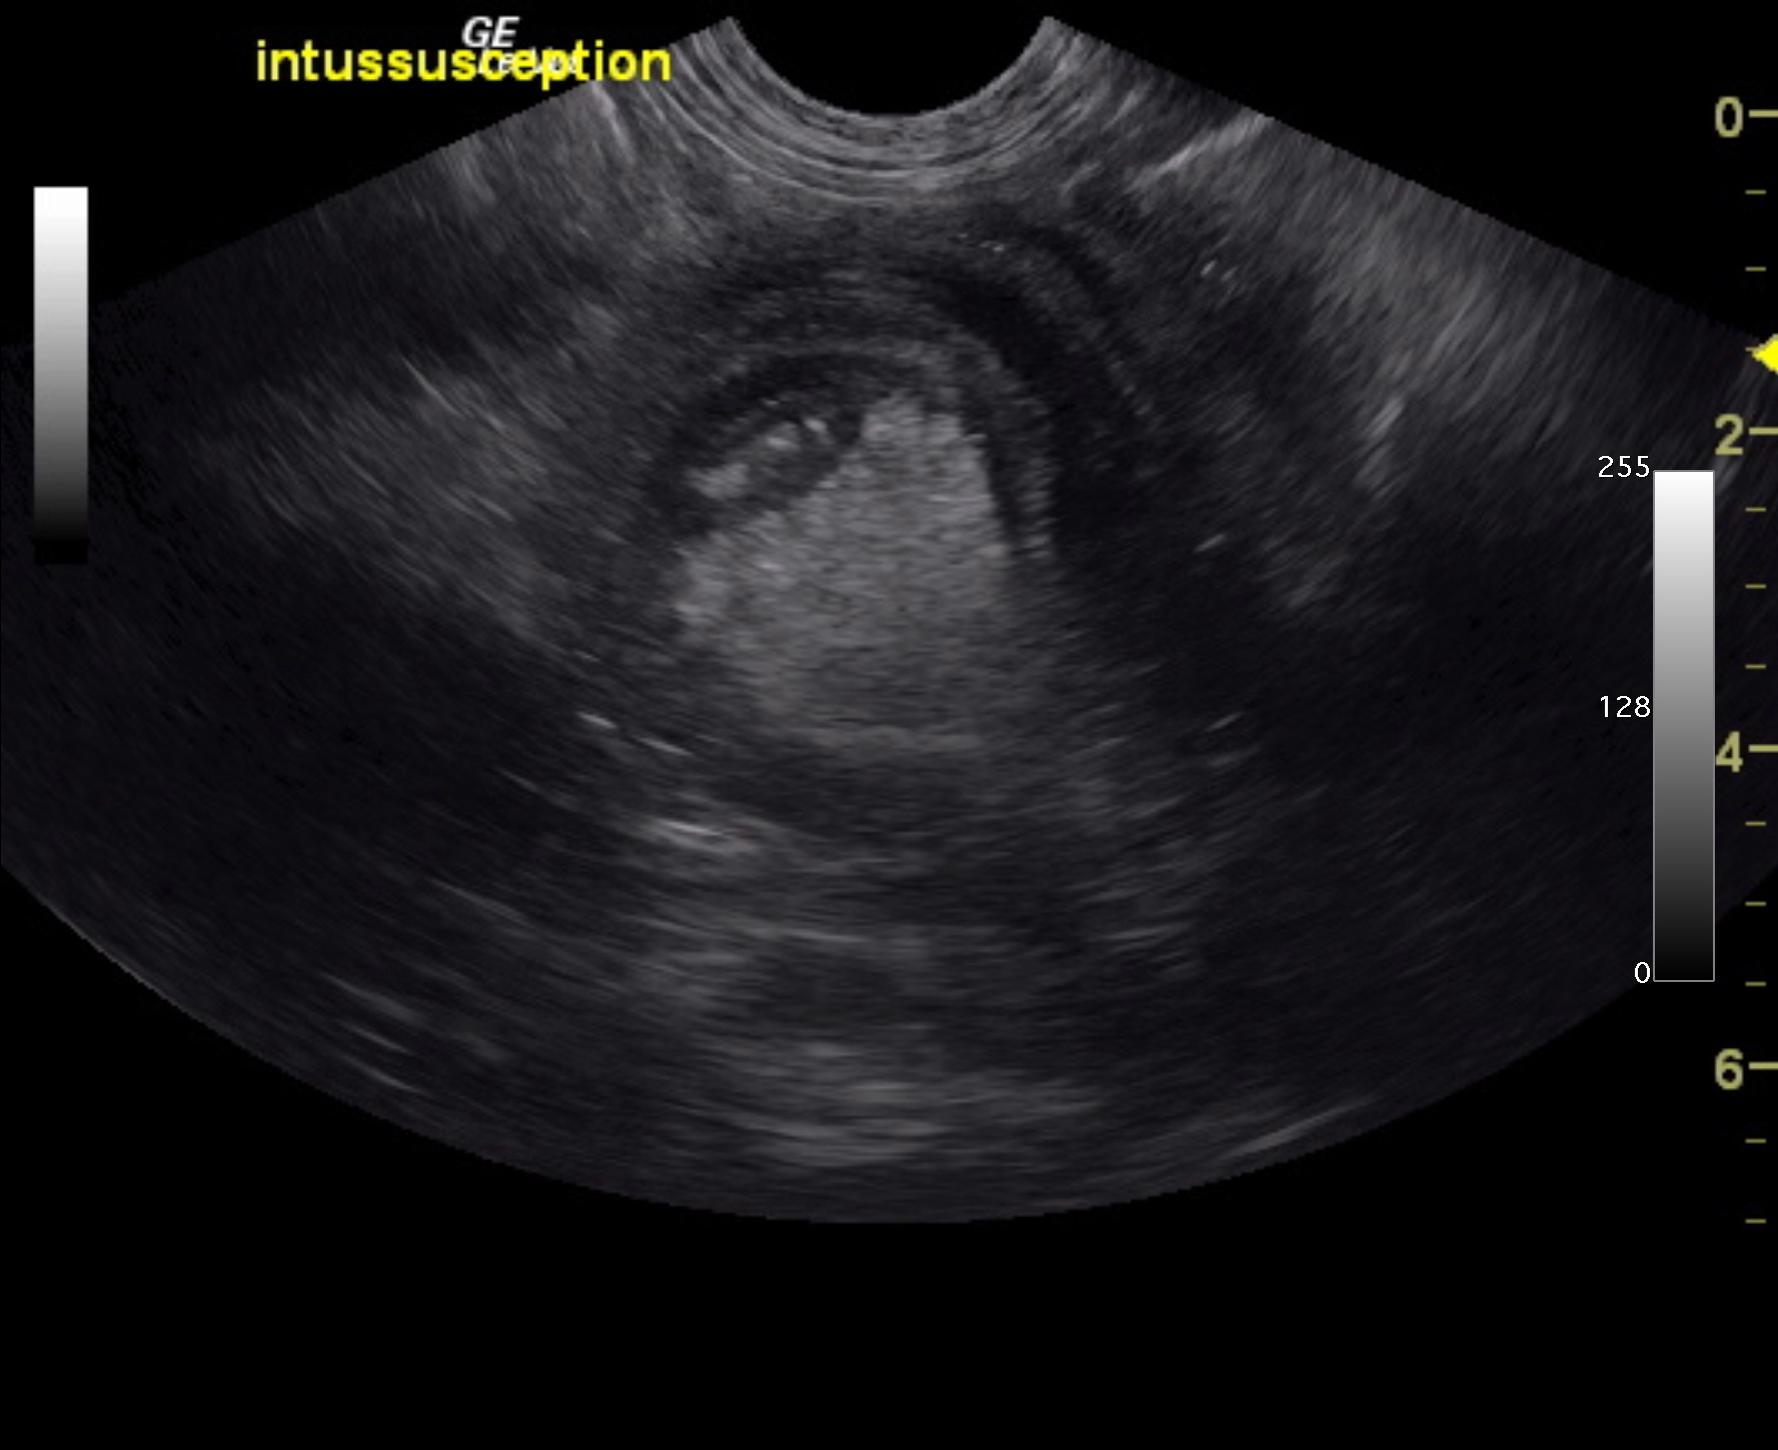

A 6-month-old intact male Labrador was presented for evaluation of diarrhea and vomiting for approximately 1 week and more recently only hemorrhagic diarrhea.